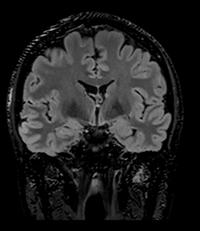

3D FLAIR with DLR. 3D FLAIR Original image. 100s, 0.5x0.5x0.6mm reconstructed

out losing time or signal. The second advantage is the reduction of image acquisition time, as we care less about the signal quality because the noise can be eleminated following the scan,” Prof. Dousset said.

In particular DLR has an important clinical impact in anatomical regions that require a very high resolution, for example parts of the hippocampus and the claustrum.

“The DLR brings a spatial resolution that I have never seen before in neurologic imaging. I recently pointed out a brain area, for example the claustrum, that is almost invisible on standard MRI images even with very high resolution or high field devices. However, thanks

to the DLR we could highlight this kind of brain anatomy. So, indeed, there is a considerable advantage to using this technique.” Prof. Dousset said.

Prof. Tourdias worked at 7T to visualise extremely fine structures of the hippocampus while at Stanford. With DLR, he can now do this task with a 3T. “When we compared the images we realized that by pushing the 3T machine and processing with DLR that we were able to achieve a similar result to what we could achieve with 7T. I think this is the main surprise of the technology.” he said.

Original Coronal T2w image.

Coronal T2w image with DLR.

“With DLR we can achieve both high resolution images without losing time or signal and reduce the image acquisition time.”